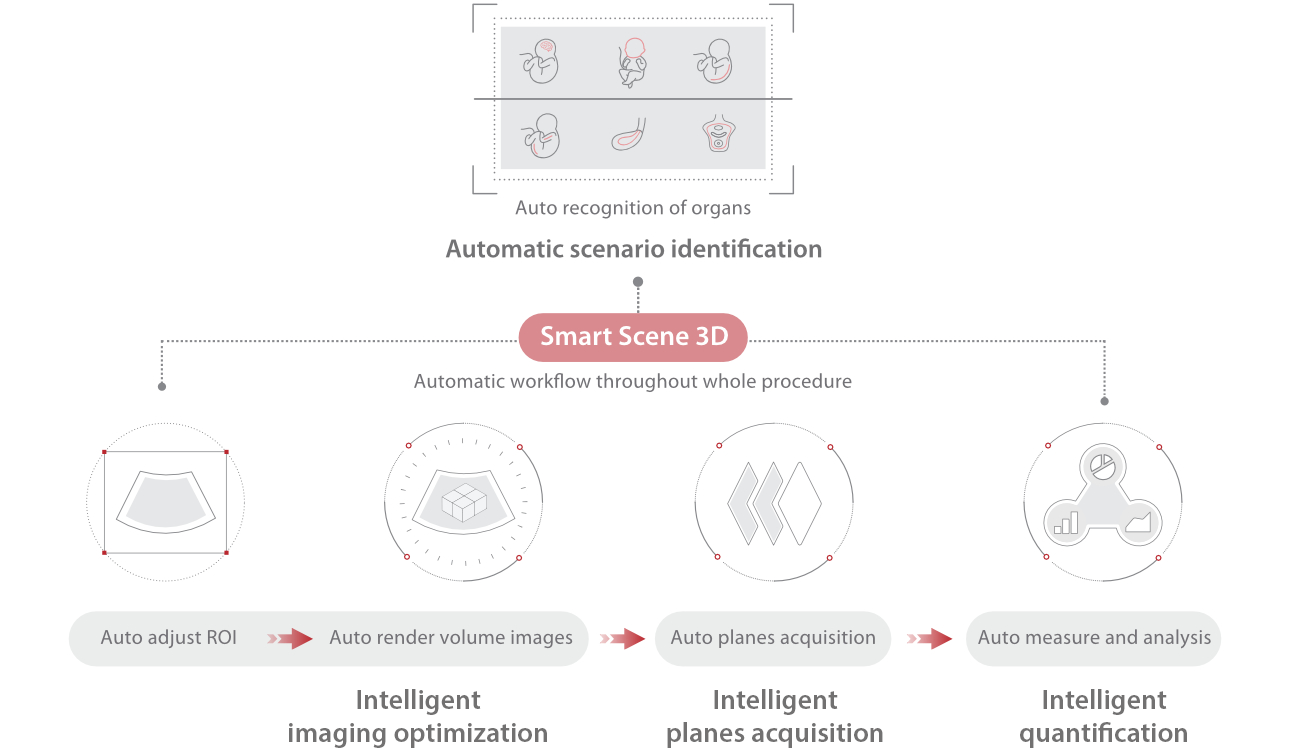

Scenario-oriented Full-stack Intelligence

The innovative Smart Scene 3D solution enables automated identification of tissue characteristics and delivers organ-specific diagnosis with full-stack intelligence throughout the entire procedure. This innovation reduces dependence on clinical skills, while elevating diagnostic accuracy, confidence, and efficiency.